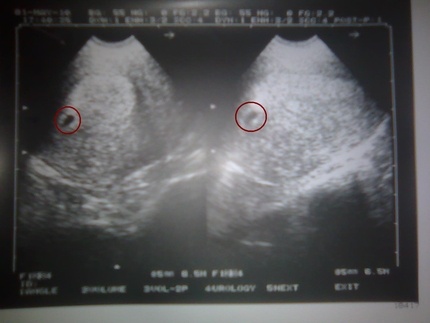

ultrasound scan in the sixth week of pregnancy

The test will certainly show two bars. HCG is one of the hormones of pregnancy, so its high content in the blood is an unequivocal confirmation. An ultrasound scanner will reveal a tiny embryo. It will look like a bright dot or comma against a dark background of the uterine cavity.

6. Inna

It was during this period that I found out that she was pregnant. I had an ultrasound scan and you know how glad I was when the doctor showed me this point. It’s like the world has turned upside down.